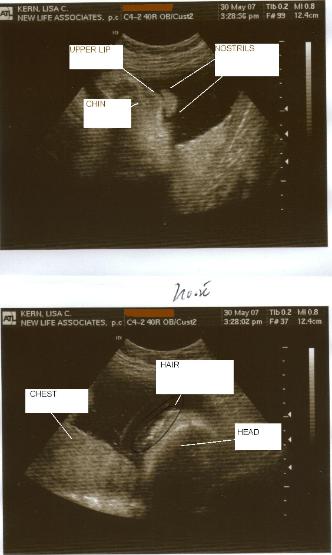

7-5-07

Baby was finally born, so I won't be ruining

any surprises now!  It's a BOY!

Click here for

more pictures of him!

Below are the two pics I had on the other

page.  The first one is a foot.  The second one

is... boy parts!